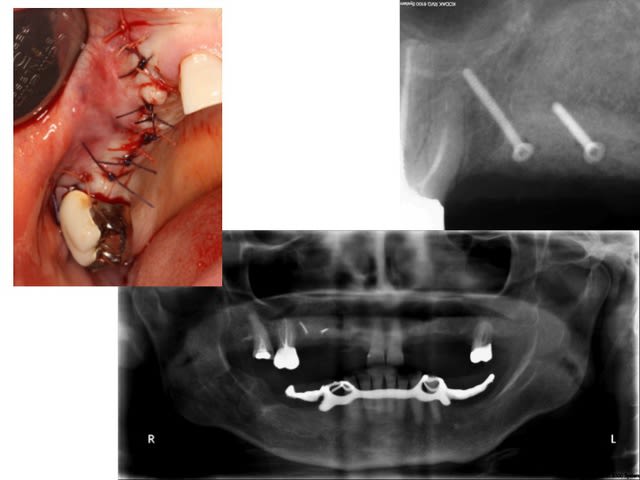

première greffe 3D

première utilisation d'allogénique. Ici c'est du Phoenix

Le principe: deux barrettes d'os autogène pour reconstruire les murs vestibulaire et palatin et servir de 'membrane'

de la poudre d'os allogénique et les restes du prélèvement pour combler l'espace créé

J'ai mis une lamelle osseuse autogène sur la partie apicale du défaut simplement posé, un peu comme sur une fenêtre de Sinus lift

pour la partie cervicale, j'ai simplement refermé le lambeau au dessus de la poudre d'os condensée

1h30 d'intervention sous AL. Suite classique. J'ai pas encore déposé les fils.......